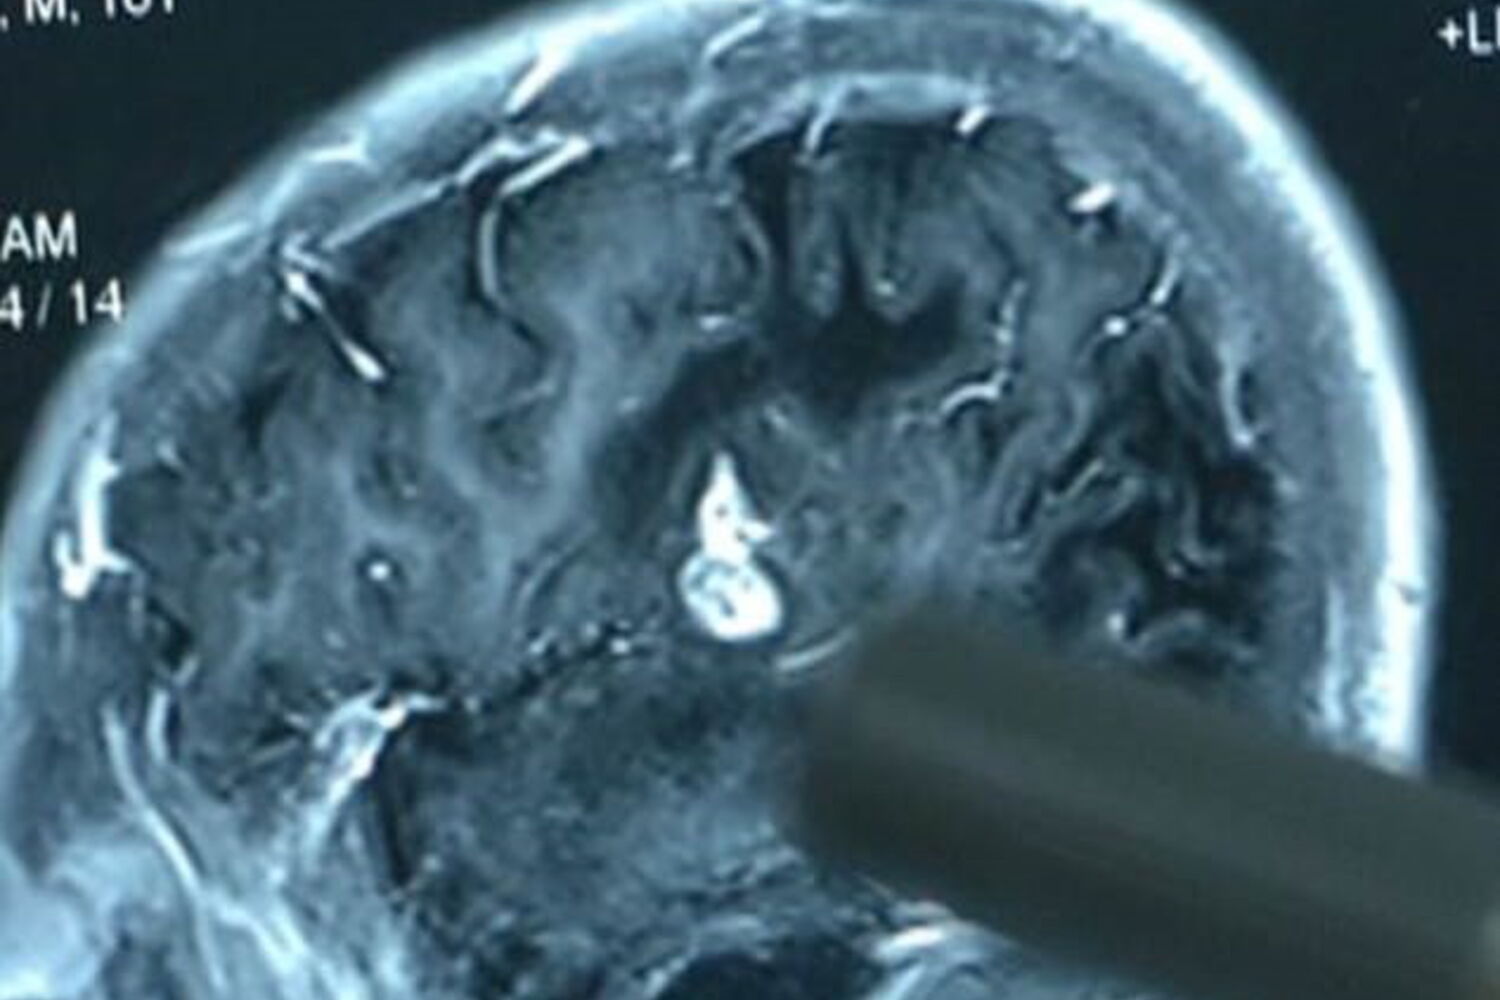

Quando os médicos fizeram a descoberta há cinco anos, através de uma ressonância magnética, decidiram que o melhor era adiar a cirurgia, uma vez que era perigoso operar a zona onde estava o parasita. Na altura, Chen foi diagnosticado com Esquistossomose, uma doença rara.

Chen começou a sentir dormência nas mãos e pés aos seis anos, mas só foi ao hospital depois de perder a sensação na parte superior direita do corpo. Além destes sintomas, o jovem também tinha dores de cabeça e náuseas.

"O parasita 'comia' o cérebro, prejudicando a sua função, o que causa dormência nas mãos e nos pés e afeta o intelectual", explicou um dos médicos envolvidos na cirurgia.